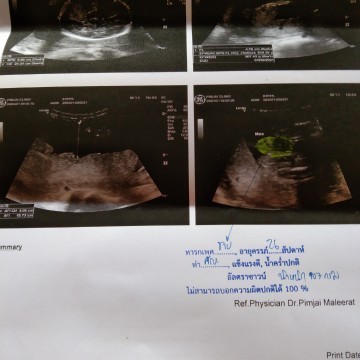

26+2วีคน้ำหนัก907กรัมปกติไหมค่ะหรือน้อยไป ลูกชายจร้า

ตามนี้เลยค่ะ